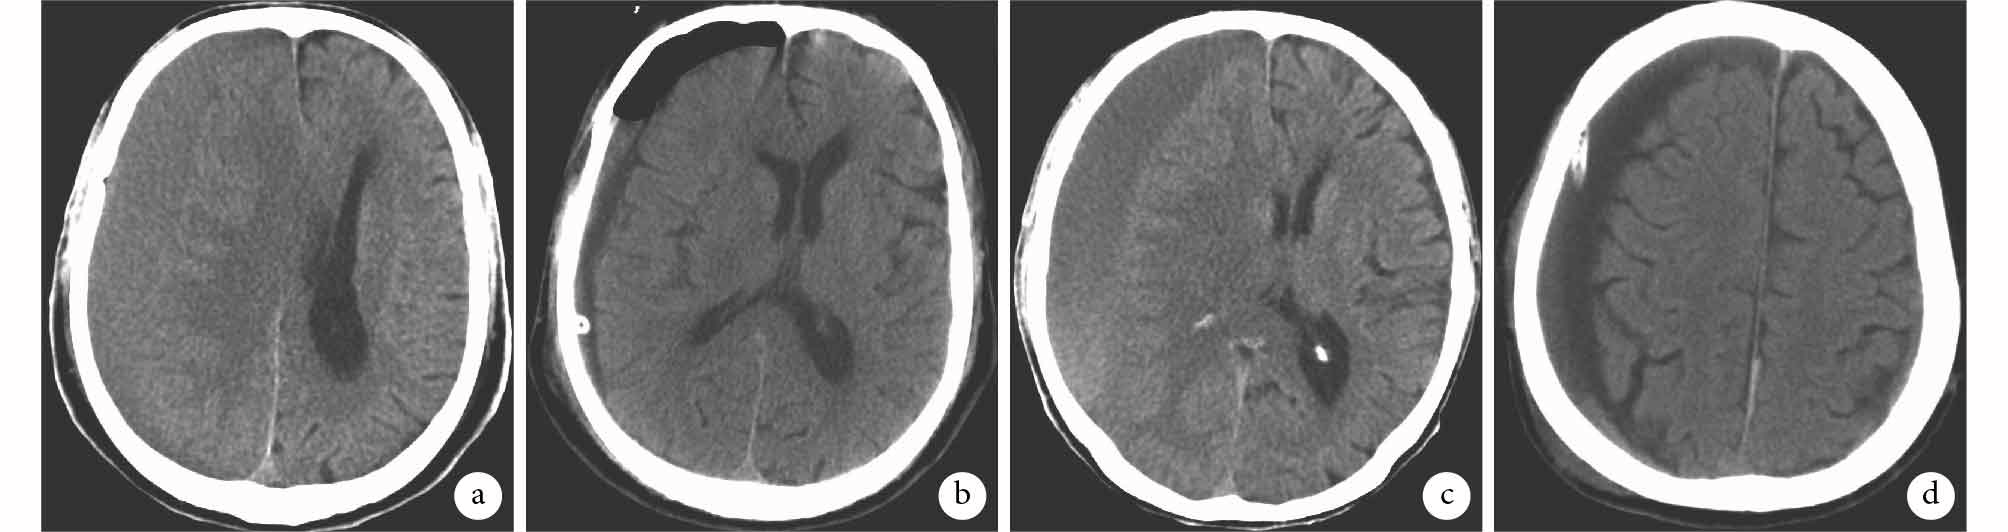

兩組患者預后較為良好,均未發生顱內感染及死亡并發癥。兩組各 3 例患者于隨訪期內血腫復發再次行手術治療,僅 1 例患者(沖洗組)發生傷口感染。術后 1 d 沖洗組患者顱內積氣量高于引流組患者,差異有統計學意義(P<0.05);兩組出院前殘余血腫量、術后出血率和血腫復發再次手術率比較差異均無統計學意義(P>0.05),見表 2。兩組典型患者 CT 影像顯示,沖洗組患者術后血腫清除較為快速、徹底,但顱內積氣量明顯高于引流組患者,見圖 1。